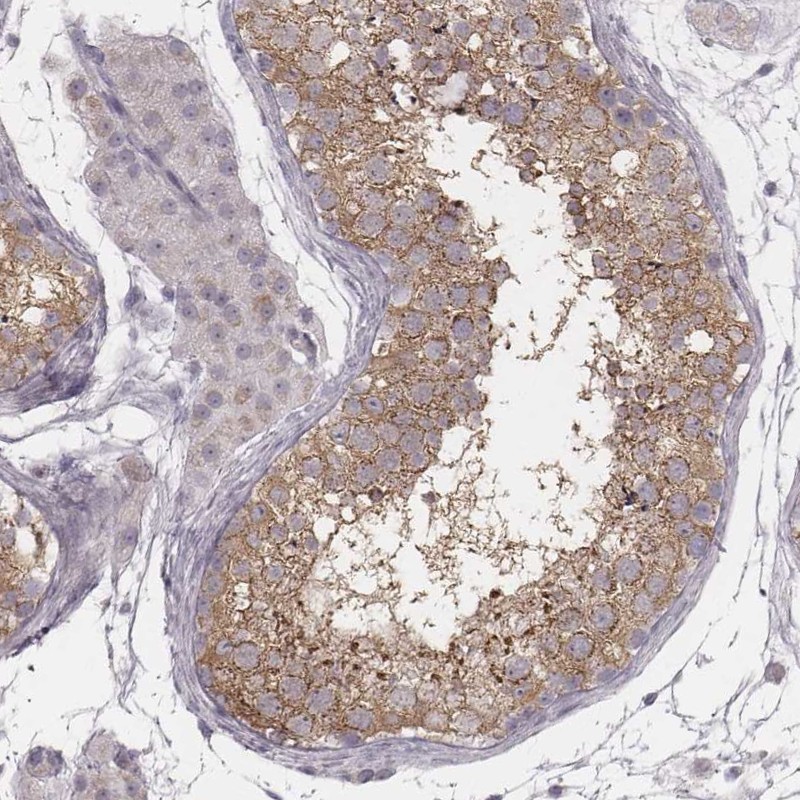

Immunohistochemical staining of human testis shows moderate cytoplasmic positivity in cells in seminiferous ducts.